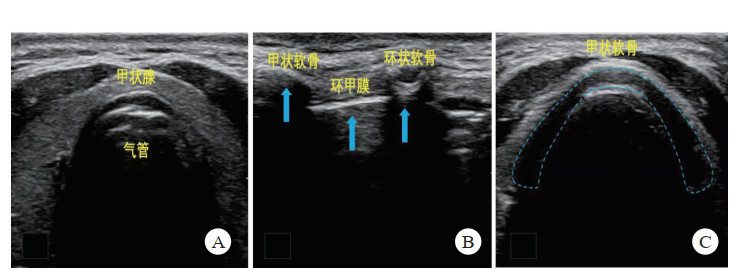

检查方法:采用高频(5.0~10.0 MHz)线阵探头,将探头放置颈部环状软骨以下,取横向切面,由下而上纵向平扫,快速扫描确定环甲膜位置(图 4)。此操作一般控制在2 min内。

| 图A-C为由环状软骨以下定位纵行向上滑动至甲状软骨; A:环状软骨以下气管处; B:甲状软骨与环状软骨交界处;C:图甲状软骨处 图 4 超声引导下横向切面环甲膜穿刺定位示意图 |